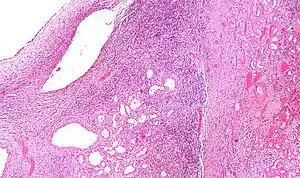

Cystic nephroma: Microscopic appearance. -

High magnification micrograph of a cystic nephroma showing the characteristic simple epithelium with hobnail morphology, and the ovarian-like stroma. H&E stain. -

The characteristics of cystic nephromas are:

- Cysts lined by a simple epithelium with a hobnail morphology, i.e. the nuclei of the cyst lining epithelium bulges into the lumen of the cysts,

- Ovarian-like stroma that has a:

- Spindle cell morphology, and has a

- Basophilic cytoplasm.